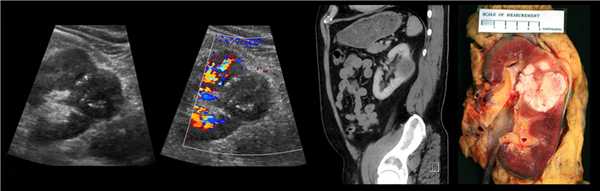

Рисунок. Двустороннее уретероцеле на УЗИ: в режиме ЦДК из верхушек уретероцеле определяется выброс мочи.

Рисунок. На УЗИ в уретероцеле определяется гиперэхогенная структура с акустической тенью — камень. Уретероцеле может являться одним из факторов, способствующих камнеообразованию.

Выполнено оперативное вмешательство, во время которого обнаружено: 1) левый мочеточник длиной около 15 см проксимально заканчивается слепо, расширен до 1,0 см в диаметре, с жидким желеобразным содержимым; 2) пролабирующий в полость мочевого пузыря интрамуральный отдел и нижняя треть мочеточника кистозно изменены, округло расширены (4,0 х 3,0 х 4,0 см); 3) стенка мочевого пузыря истончена. Полностью иссечено рудиментарное образование из стенки мочевого пузыря.

Препарат: кистевидно расширенный в нижней трети мочеточник, слепо заканчивающийся проксимально.

Гистологическое заключение: полостное образование, представленное всеми структурными элементами мочеточника, с дегенеративными изменениями слизистой и участками фиброза, гипертрофии мышечных слоев. Элементов почки и неопластических очагов в препарате не выявлено.